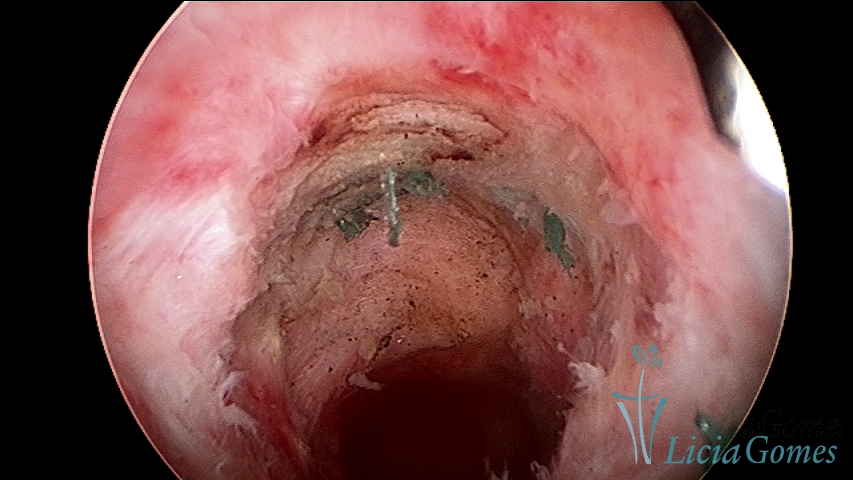

Retraction of a cesarean section scar with a non-absorbable suture for 30 years; resection with bipolar energy.

×

After the resection of the suture in Retraction of a cesarean section scar